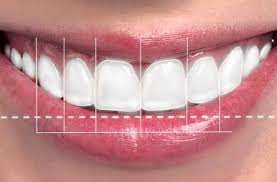

Smile Analysis (Mock-up)

Your Smile Analysis begins with an examination and a personal consultation with your dentist. Your dentist will evaluate the health and appearance of your teeth and gums to ensure that more pressing concerns such as decay or infection are not present. Then, your lip line, facial shape, jaw angle and eye symmetry are examined, photographs are taken and three dimensional plaster study models are fabricated

Mockup